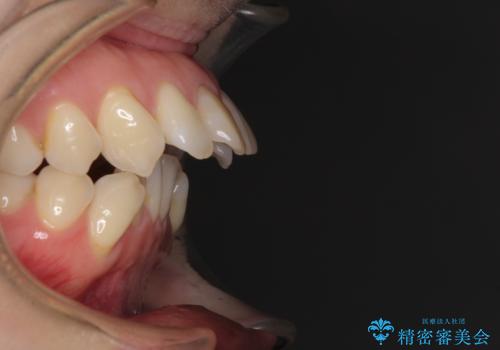

- 上の前歯の飛び出した感じを改善したいとのことで来院された患者様です。

上顎左右第一小臼歯2本、下顎左右第二小臼歯2本を抜歯し、ワイヤー装置にて口元を引っ込めるよう矯正治療を行うこととしました。

上下の前歯に隙間が空くほど上顎前歯が前に飛び出していましたが、抜歯矯正により上下前歯がぴったりと付くほど口元を引っ込めることができました。